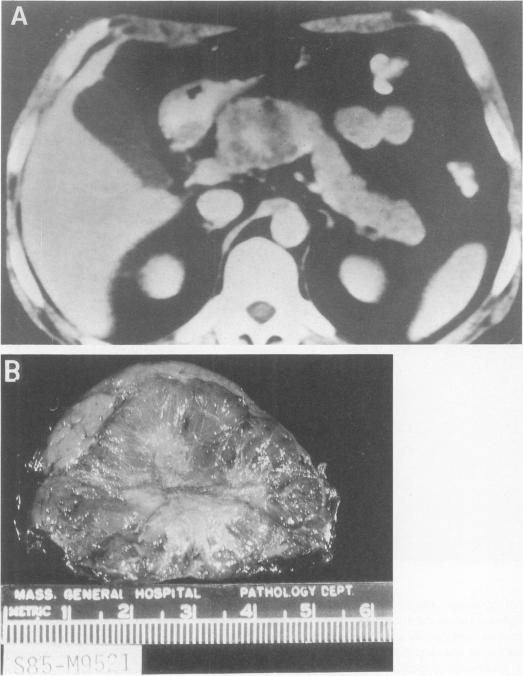

Within a 12-year period we treated 67 patients (49 women, 18 men; mean age, 61 years) with cystic neoplasms of the pancreas, including 18 serous cystic adenomas, 15 benign mucinous cystic neoplasms, 27 mucinous cystadenocarcinomas, 3 papillary cystic tumors, 2 cystic islet cell tumors, and 2 cases of mucinous ductal ectasia. Mean tumor size was 6 cm (2 to 16 cm). In 39% the patients had no symptoms, and in 37% the lesions had been misdiagnosed as a pseudocyst. Computed tomography was useful for detection, for distinguishing the microcystic subgroup of serous cystadenoma, and for showing rim calcification (all 7 cases were malignant) but was not reliable for distinguishing neoplasm from pseudocyst, serous from mucinous tumors, or benign from malignant. Arteriography showed hypervascularity in 4 of 10 serous adenomas, 3 of 11 mucinous carcinomas, and 1 of 1 papillary cystic tumors. Endoscopic pancreatography showed no communication with the cyst cavity in 37 of 37 cases of cystic neoplasms but opacified the ectatic ducts in 2 of 2 cases of mucinous ductal ectasia. Stenosis or obstruction of the pancreatic duct indicated cancer. The tumor was resected by distal pancreatectomy in 25 patients, by proximal resection in 29, and by total pancreatectomy in one, with no operative deaths. Forty-four per cent of the tumors were malignant. In 10 cases the tumor was unresectable because of local extension or distant metastases, and those patients died at a mean of 4 months. Seventy-five per cent of those resected for cure are alive without evident recurrence. Because the epithelial lining of the tumor was partially (5% to 98%) absent in 40% to 72% of cases of the major tumor types, and the mucinous component comprised only about 65% of mucinous cystadenoma lining, misdiagnoses on frozen and even permanent sections were made. Mitoses and histologic solid growth correlated with malignancy. Neuroendocrine elements were seen in 87% of benign and 47% of malignant mucinous tumors. It is recommended that the terms macrocystic and microcystic be abandoned in favor of the histologic designations serous and mucinous. Incomplete examination of the cyst wall can be misleading, however. It is suggested that mucinous ductal ectasia be recognized separately from cystic tumors and that all of these lesions be resected, with the possible exception of asymptomatic confirmed serous cystadenomas.

在12年期间,我们治疗了67例胰腺囊性肿瘤患者(49例女性,18例男性;平均年龄61岁),其中包括18例浆液性囊腺瘤、15例良性黏液性囊性肿瘤、27例黏液性囊腺癌、3例乳头状囊性肿瘤、2例囊性胰岛细胞瘤以及2例黏液性导管扩张症。肿瘤平均大小为6 cm(2至16 cm)。39%的患者无症状,37%的病变曾被误诊为假性囊肿。计算机断层扫描(CT)有助于检测、区分浆液性囊腺瘤的微囊性亚组以及显示边缘钙化(所有7例均为恶性),但在区分肿瘤与假性囊肿、浆液性肿瘤与黏液性肿瘤或良性与恶性方面并不可靠。动脉造影显示,10例浆液性腺瘤中有4例、11例黏液性癌中有3例以及1例乳头状囊性肿瘤中有1例表现为血管增多。内镜胰胆管造影显示(37例囊性肿瘤中的)37例囊肿腔与胰管不相通,但(2例黏液性导管扩张症中的)2例扩张导管显影。胰管狭窄或阻塞提示癌症。25例患者行胰体尾切除术,29例行胰头切除术,1例行全胰切除术,无手术死亡病例。44%的肿瘤为恶性。10例患者因局部侵犯或远处转移无法切除肿瘤,这些患者平均4个月后死亡。75%接受根治性切除的患者存活且无明显复发。由于在主要肿瘤类型的40%至72%病例中肿瘤上皮衬里部分(5%至98%)缺失,且黏液性成分仅占黏液性囊腺瘤衬里的约65%,因此在冷冻切片甚至永久切片上都出现了误诊。有丝分裂和组织学实性生长与恶性相关。在87%的良性和47%的恶性黏液性肿瘤中可见神经内分泌成分。建议摒弃“大囊性”和“微囊性”术语,而采用组织学名称“浆液性”和“黏液性”。然而,对囊肿壁检查不完整可能会产生误导。建议将黏液性导管扩张症与囊性肿瘤分开识别,并且除无症状的确诊浆液性囊腺瘤外,所有这些病变均应切除。